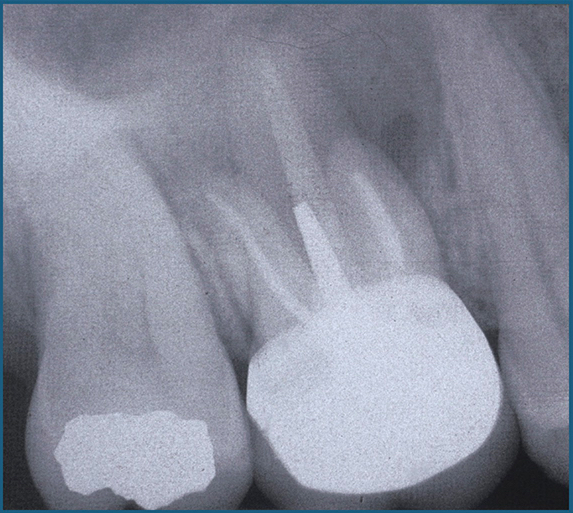

Ensuite, Christine Bach (entretien à lire ici), chirurgien ORL à l’hôpital Foch, nous alertera sur les pathologies sinusiennes importantes. Mais aussi, elle débattra, avec la complicité de Jean-Yves Cochet, endodontiste, sur les moyens diagnostiques permettant de différencier l’étiologie sinusienne de l’étiologie endodontique. Et cela, bien sûr, à travers différentes situations cliniques.

Jean-Yves Cochet (entretien à lire ici) prendra les manettes en début d’après-midi pour dresser un état clinique des pathologies sinusiennes d’origine endodontique. Il nous fera part de son expertise en tant qu’endodontiste régulièrement confronté à des cas complexes. Il délivrera les clés thérapeutiques pour optimiser la guérison grâce aux traitements endodontiques mais, nous alertera, aussi, sur les cas où ces traitements sont exposés à un risque d’échec.

- Lecture de l’imagerie sinusienne : repérer les structures et anomalies anatomiques

- Douleurs et symptômes, pathologie sinusienne ou dentaire ?

- Traitements endodontiques et chirurgicaux : indications, échecs et limites